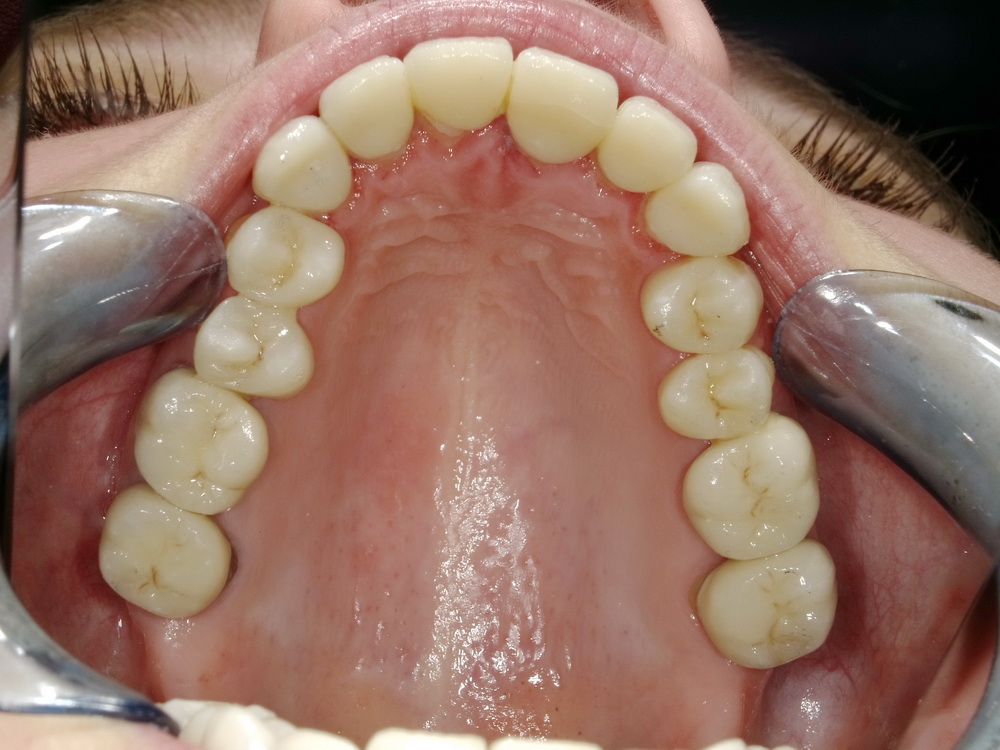

Totalrekonstruierte CMD-Patientin aus dem Münsterland zum Abschlussbefund

Die Patientin ist praktisch beschwerdefrei: 0-1.

Die Behandlung wurde mit Erfolg abgeschlossen, die Patienitn aufwändig instruiert.